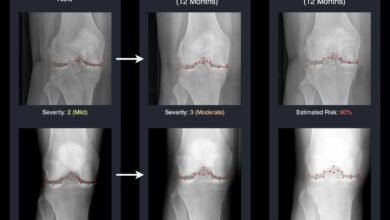

AI Brings Tomorrow’s X-Rays To Life, Helping Doctors Fight Arthritis Sooner

AI predicts osteoarthritis progression. Credit: University of Surrey An AI system developed at the University of Surrey can predict future…